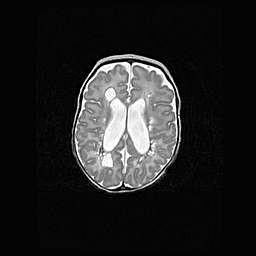

Церебральная ишемия II.

Возраст: 5 дней

Вес: 3400 г

Пол: женский

Окружность головы: 35 см

Срок гестации: 39 недель

Церебральная ишемия – это заболевание, характеризующееся недостаточностью (гипоксией) либо полным прекращением (аноксией) снабжения мозга кислородом по причине закупорки одного или нескольких сосудов. Это приводит к  что метаболическим расстройствам различной степени тяжести в тканях головного мозга, развитию коагуляционных некрозов и гибели нейронов.